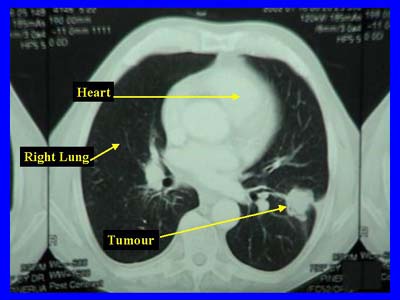

3. Location in the Lungs

- SCLC: Typically central (near the bronchi).

- NSCLC: Can be central (squamous) or peripheral (adenocarcinoma).

4. Metastasis & Prognosis

- SCLC: Highly metastatic, often diagnosed at an advanced stage. Poor prognosis.

- NSCLC: Spreads more slowly, often diagnosed earlier, and has a better prognosis.